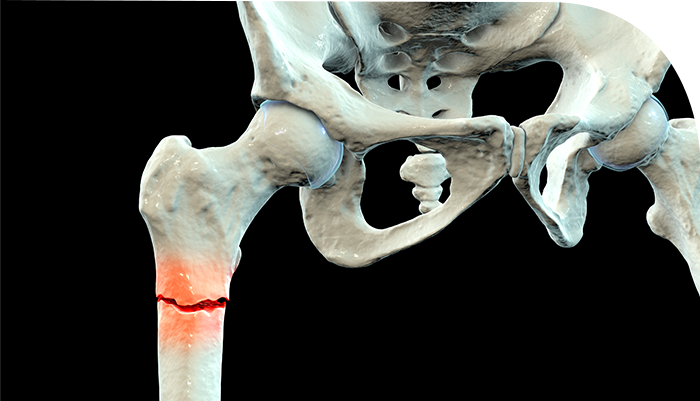

À¯ÇÕÀº °ñÀý ÈÄ »À°¡ Ä¡À¯µÇ¾î ºÙÀº »óŸ¦ ÀǹÌÇÕ´Ï´Ù.

ºÒÀ¯ÇÕÀº »À°¡ ºÙÁö ¾ÊÀº »óÅ·Π°ñÀý ºÎºÐÀÇ Ä¡À¯ °úÁ¤ÀÌ º¸ÀÌÁö ¾Ê´Â »óŸ¦ ÀǹÌÇÕ´Ï´Ù.

ºÒÀ¯ÇÕÀÇ °æ¿ì °ñÀý¼±ÀÌ ¹æ»ç¼±»ó¿¡¼­ Áö¼ÓÀûÀ¸·Î º¸À̰ųª °ñÀý ³¡ ºÎÀ§¿¡ °æÈ­°¡ È®Àε˴ϴÙ.

°¡°ñÀ̶õ »À°¡ °ñÀýÀÌ µÈ ÀÌÈÄ ºÙ´Â °úÁ¤¿¡¼­ »ý±â´Â Á¤»óÀûÀÎ »À Á¶Á÷Àε¥,

ºÒÀ¯ÇÕ¿¡¼­ ¿øÀΰú Á¾·ù¿¡ µû¶ó¼­ °¡°ñ Çü¼ºÀÌ ºñ´ëÇϰųª ¾ø±âµµ ÇÕ´Ï´Ù.